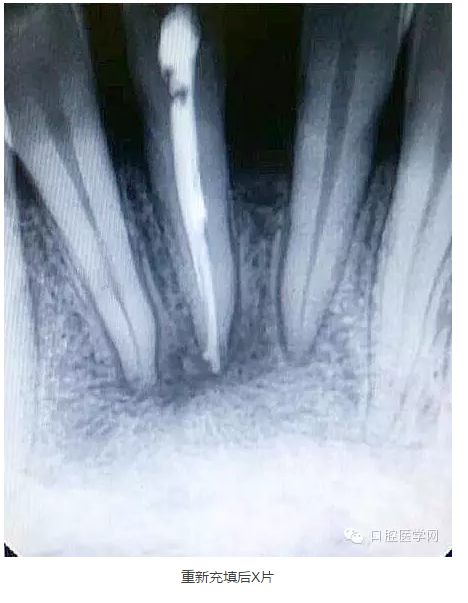

9.觀察一個月后打開暫封物拔出牙膠尖,檢查根管內(nèi)是否有滲出液,如果根管基本干燥,可再次沖洗消毒后根充,仍有滲出液者應(yīng)查明情況繼續(xù)治療。

下面是一例 今年年初治療的下前牙根尖囊腫病例,患者因故未能按時復診,最近才來。